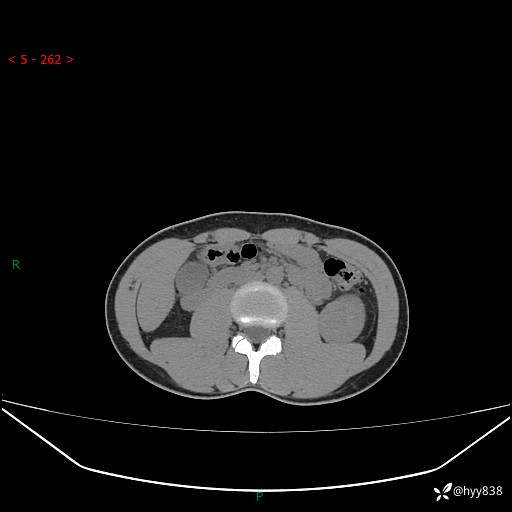

年轻男性,发现左肾占位1天。“非好病例”我不发,误诊率高---(有结果)

现病史:患者昨日中午进食后出现明显腹痛,腹泻,在我院急诊科行补液及对症治疗,双肾输尿管彩超提示左肾占位(5.2*4.3cm),平素无明显腰痛,无再发肉眼血尿等情况,现为求处理左肾占位,遂来我院,门诊以左肾占位收治入院。 患者起病以来,精神、食欲、睡眠尚可,大便可,小便如上,体力体重无明显下降。

双肾CT平扫+增强(三期)